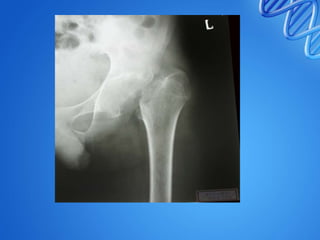

• 4. Advanced arthritis with subluxation /

dislocation :

• Furhter destruction of acetabulum , head ,

capsule and ligaments.

• Gross restriction of ROM

• Head – upwards and posteriorly

• Wandering / migrating acetabulum

• Mortle & pestle appearance

• Reduced joint space

Radiograph showing a ‘travelling’ or

‘wandering’ right hip